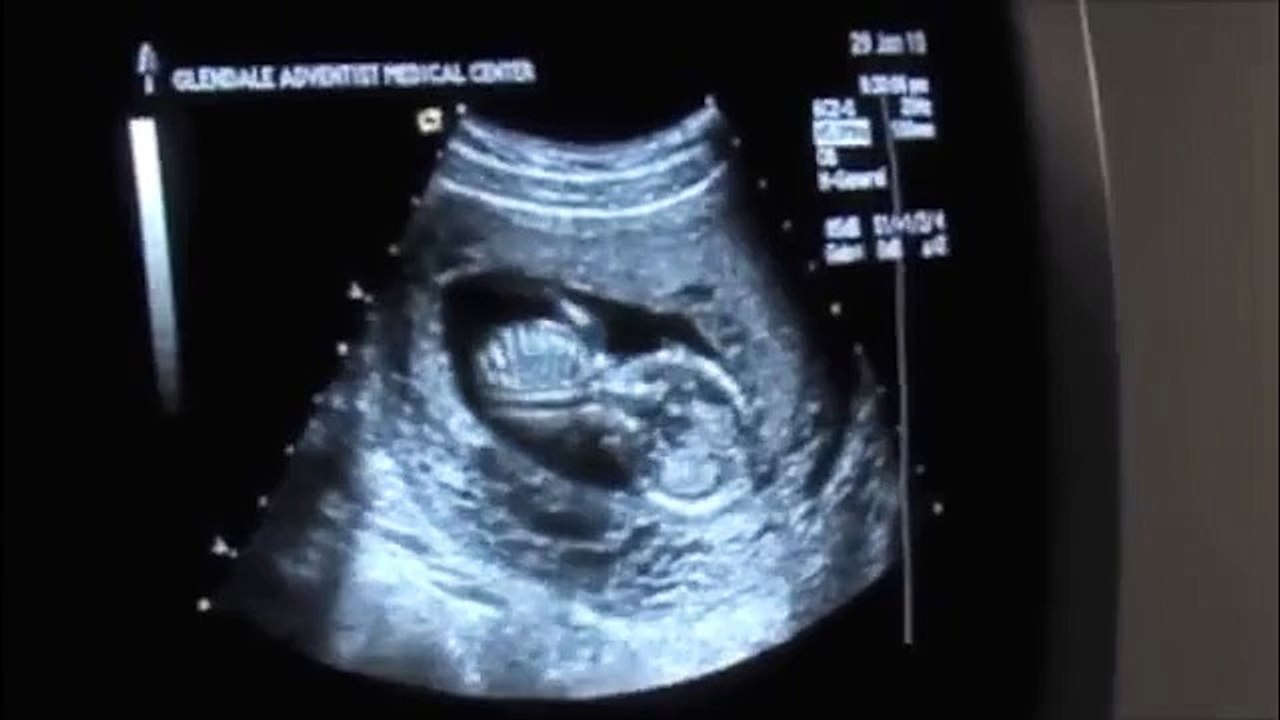

An ultrasound is routinely used at different stages of the pregnancyWhile most practitioners will wait until at. Hello loves welcome back to another video. We can accurately tell the gender at 14 weeks.

If the caudal notch is pointing upward at more than a 30. Early Gender Ultrasound at 14 Weeks. If the caudal notch is pointing upward at more than a 30-degree angle then the fetus is a boy.

Our gender reveal video. Ultrasounds may reveal sex organs by 14 weeks but they arent considered fully accurate until 18 weeks. I am having mine this Saturday at 14w3d but we are going to an ultrasound.